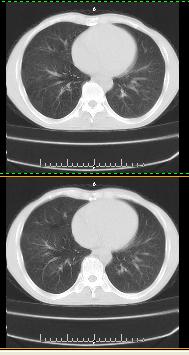

以下是引用liaoqiang在2008-3-21 17:45:00的发言:[br]右上叶尖段、后段有多发小结节和小条状影。考虑感染(结核可能性大。)。建议治疗后复查。

以下是引用王2008在2008-3-21 17:38:00的发言:[br]右上叶后段沿纹理走向呈串珠状.边缘欠清密度增高影,局部胸膜增厚.[br]考虑1.右上支扩可能.2.右上炎症.建议治疗后复查.请各位老师指教.

以下是引用lj11119999在2008-3-21 18:15:00的发言:[br]右上叶尖段、后段有多发小结节和小条状影。考虑感染(结核可能)建议进一步检查!